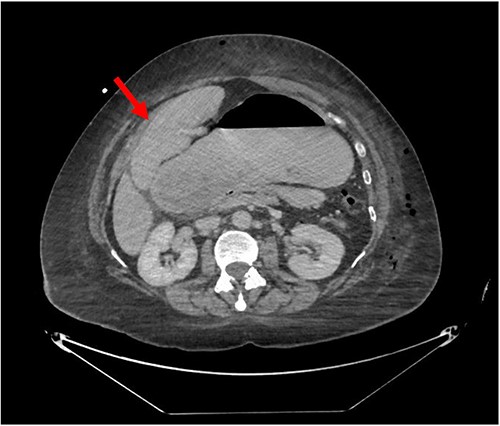

Despite the insertion of the NGT yielding 1500 cc output in 24 hours, the patient continued to experience severe abdominal pain. Urgent abdominal and pelvic computed tomography (CT) scans were taken, as seen in Figs 2–4. The CT scans showed gastric distension and the spleen positioned anteriorly in the right upper quadrant. Consequently, the decision was made to promptly bring the patient to the operating room for a diagnostic laparoscopy with plan to detorse the spleen.

CT of the abdomen and pelvis (axial slice) showing gastric distention and the spleen positioned anteriorly in the right upper quadrant.

Our patient’s pre-existing conditions presented challenges in distinguishing between expected postoperative discomfort and potential complications following her recent adrenalectomy. This uncertainty, combined with a normal WBC count, absence of fever, and regular bowel function, initially led the medical team to attribute her pain to the recent surgery two days prior, delaying her diagnosis and potentially exacerbating her condition. Subsequent imaging became imperative, revealing a persistent large gastric bubble despite NGT decompression, and malposition of the spleen (Fig. 3). This prompted immediate preoperative measures to facilitate a diagnostic laparoscopy.